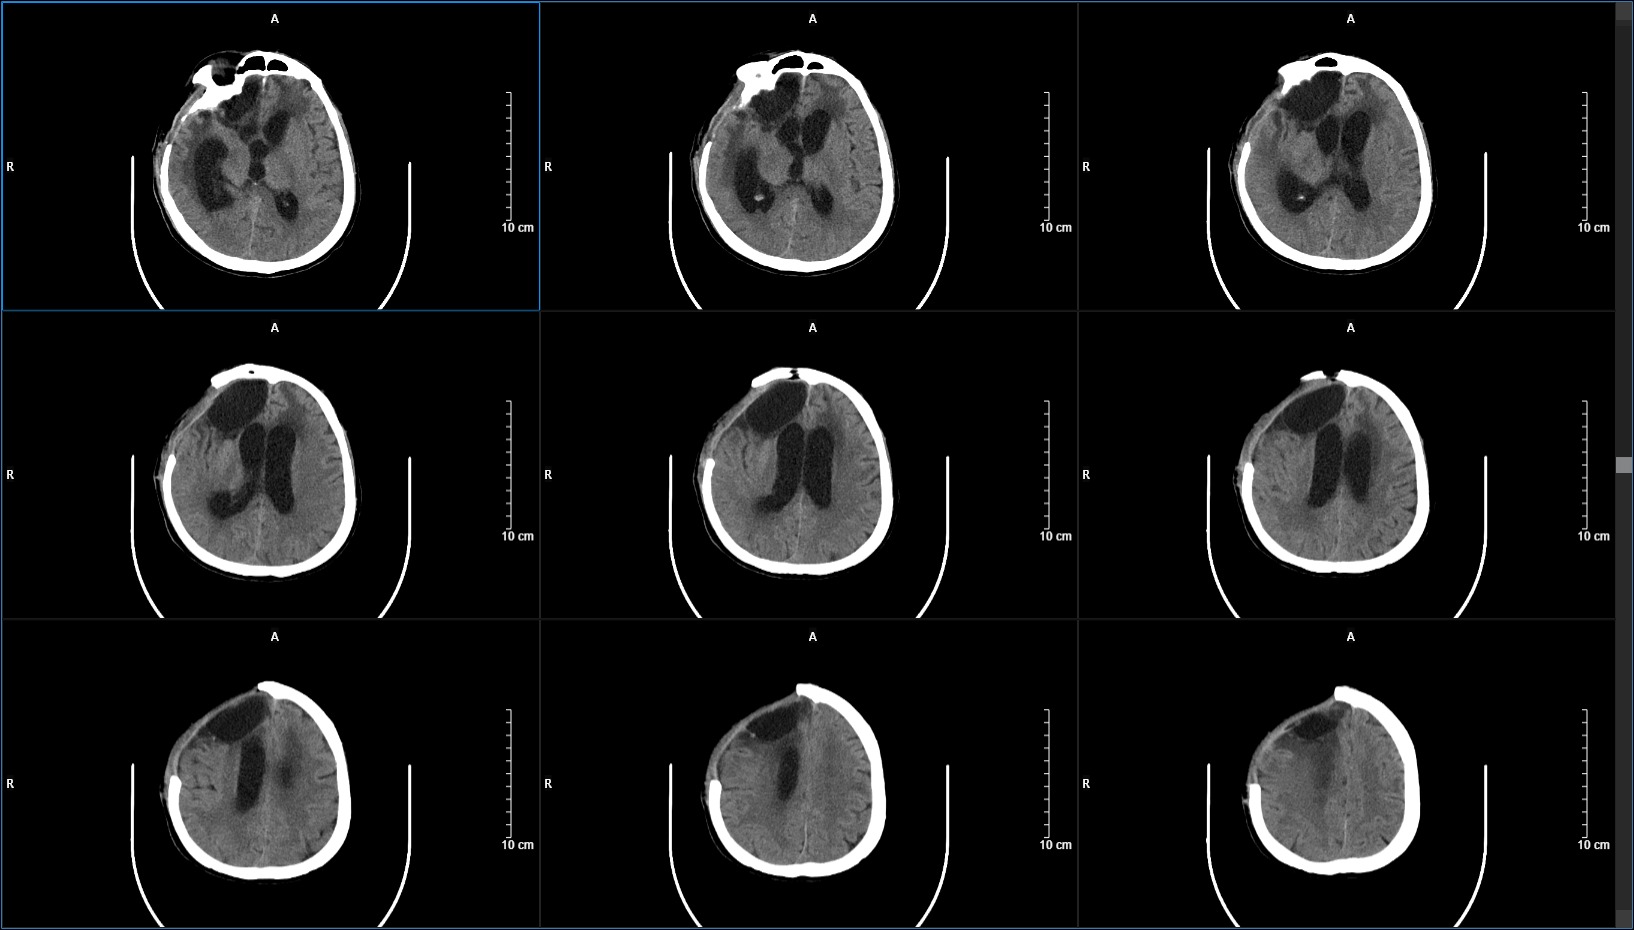

CT显示脑室饱满,颅压220mmH2O,行腰大池引流术,持续引流一周后(期间查脑脊液各项指标均正常),患者症状较入院时好转,查体能简单遵嘱动作,遂行脑室-腹腔分流术。